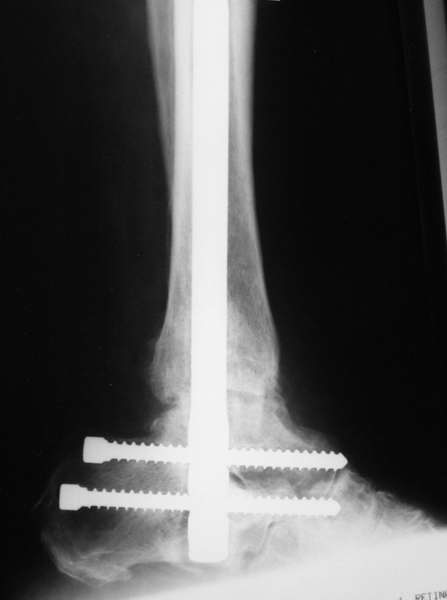

Можно: 65-летняя пациентка, оперирована по поводу несросшегося в гипсе перелома лодыжек с патологической вальгусной установкой стопы и выраженным нарушением опрной функции. Оперирована через 6 месяцев после травмы. Рентгенограммы через 4 месяца после операции.

С уважением, А.Семенистый.